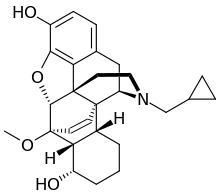

Several semi-synthetic opioids were developed in Germany in the 1910s. The first, oxymorphone, was synthesized from thebaine, an opioid alkaloid in opium poppies, in 1914.[228] Next, Martin Freund and Edmund Speyer developed oxycodone, also from thebaine, at the University of Frankfurt in 1916.[229] In 1920, hydrocodone was prepared by Carl Mannich and Helene Löwenheim, deriving it from codeine. In 1924, hydromorphone was synthesized by adding hydrogen to morphine. Etorphine was synthesized in 1960, from the oripavine in opium poppy straw. Buprenorphine was discovered in 1972.[228]